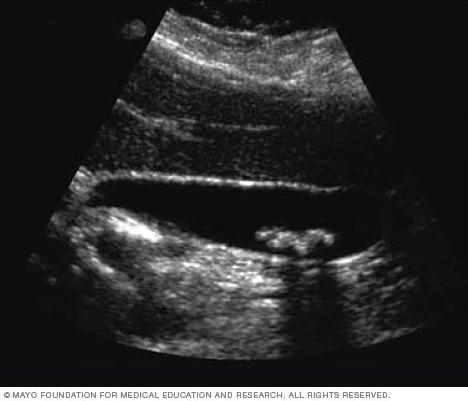

Ultrasound image of a liver tumor

Ultrasound of liver tumor

An ultrasound uses sound waves to create an image. This ultrasound shows a noncancerous liver tumor.